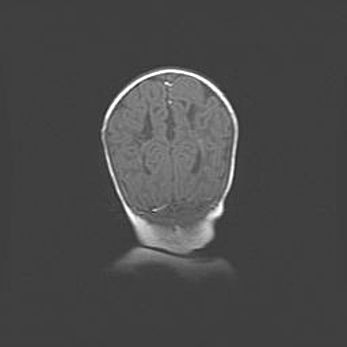

Открытая гидроцефалия.

Возраст: 9 месяцев 12 дней

Вес: 6800 г

Пол: мужской

Окружность головы: 41,5 см

Срок гестации: 28 недель

Гидроцефалия головного мозга у новорожденных имеет характерный признак: опережающий рост окружности головы приводит к визуально хорошо определяемой гидроцефальной форме сильно увеличенного в объёме черепа. Детские неврологи определяют следующие симптомы гидроцефалии у грудничков: выбухающий напряжённый родничок, частое запрокидывание головы, смещение глазных яблок к низу.